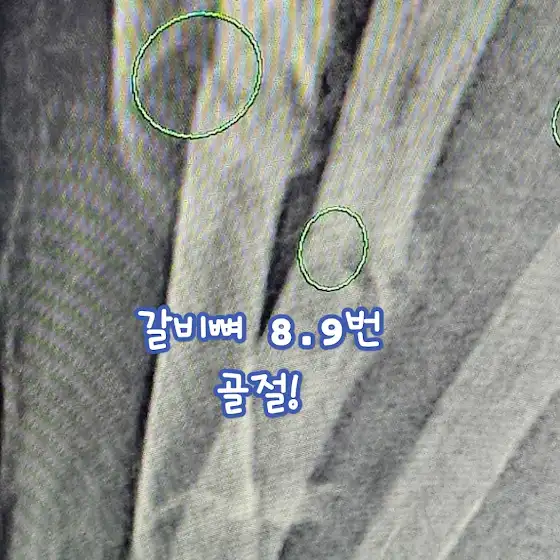

제가 지금 ㅋ

갈비뼈 골절 이라 ..

오늘은 일단 쉬께요!